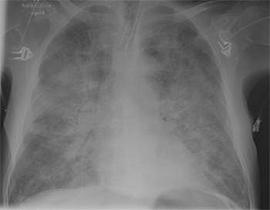

Foto radiográfica de un edema pulmonar

Los atmosferonautas en la cápsula chamuscada desarrollan un

edema pulmonar (conjunto de agua en el pulmón) y primeros

auxilios no reciben: Los atmosferonautas desmayados siguen

respirando el humo tóxico. Los alvéolos pulmonares se

desarrollan mal por los gases corrosivos y van a ser

esponjosos y permeables. Los alvéolos dañados absorban

líquido de la circulación sanguínea. Así los alvéolos

pulmonares no pueden absorber aire respiratorio más, y

lentamente los atmosferonautas se ahogan. Wisnewski: "El

hombre se ahoga en su propio líquido corporal", eso es un

edema pulmonar (Wisnewski, p.103).

El tiempo mínimo para desarrollar un edema pulmonar son 15 a

20 minutos. Pero la formación de un edema pulmonar por la

respiración de gases de lucha - son similares a los gases de

plástico quemado - dura algunas horas. Con todo eso se ve

que los atmosferonautas al menos han vivido 10 a 15 minutos

todavía. Eso hubiera sido tiempo para dar primeros auxilios

exitosos (Wisnewski, p.103).